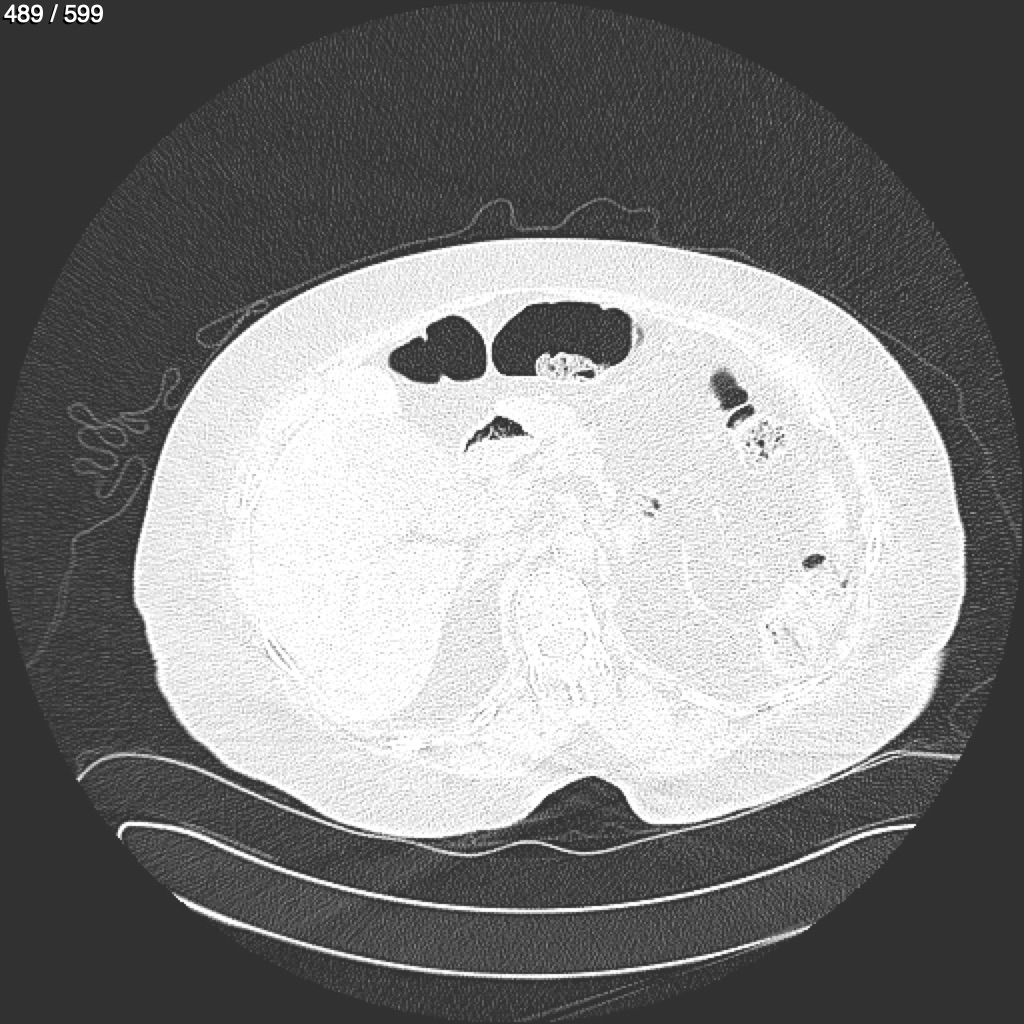

Home G​l​o​r​i​a​ ​G​l​a​d​y​s​ ​B​e​a​s​l​e​y​ ​-​ ​T​ó​r​a​x​ ​T​o​r​a​x​_​S​i​m​p​l​e​ ​(​A​d​u​l​t​o​)